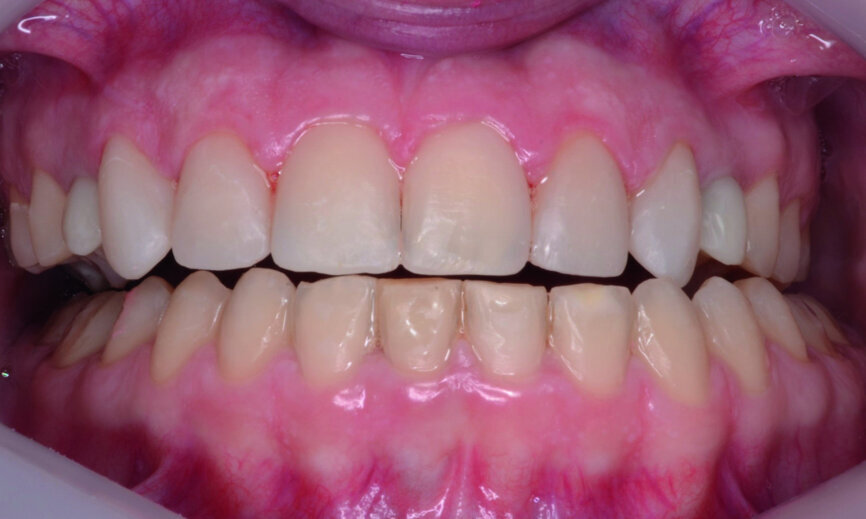

At the end of orthodontic treatment, gingival margins were well aligned, midlines were centred and canines and first premolars were positioned to facilitate the restorative phase of treatment (Figs. 34–36). At this phase, a final CR mounting and wax-up was performed (Figs. 37–39), as well as the anterior teeth restorations (Fig. 40).

Orthodontic treatment has improved both dental and facial aesthetics (Figs. 41–47) and the functionality of the occlusion (Figs. 48–52).